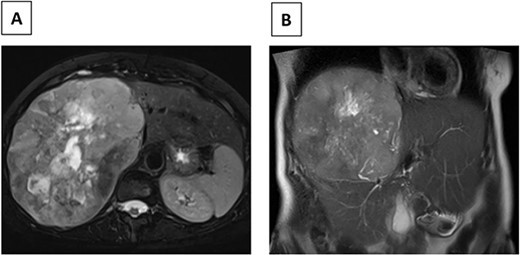

In July 2022, the patient developed right upper-quadrant pain prompting an abdominal ultrasound, which demonstrated a large mass in the right lobe of the liver. An abdominal MRI revealed a 23 × 17 cm heterogeneous mass with mild arterial enhancement in the right lobe of the liver with mass effect on the intrahepatic inferior vena cava (IVC) (Fig. 1). An enhancing L1 vertebral lesion was also discovered on the MRI with a differential diagnosis of atypical intraosseous hemangioma versus metastatic disease. Hepatic function tests as well as tumor markers including AFP, CEA, CA-125 and CA19-9 were normal. A CT guided biopsy of the liver lesion was consistent with metastatic meningioma. Pathologic review and comparison with the initial cranial meningioma revealed a similar immune profile (positive for SSTR2a, EMA, and FL1 negative for CD34) and mitotic rate (2 mitoses/10 HPF). A (18F) FDG PET/CT scan demonstrated a large right hepatic mass with significant metabolic activity, although the lesion in L1 was not PET avid. The patient was discussed at a multidisciplinary tumor board and surgical resection was recommended given the patient’s symptomatology as well as the large size and mass effect on the IVC.

(A) Axial MRI image (T2) of R hepatic lobe mass. (B) Coronal MRI image (T2) of R hepatic lobe mass.